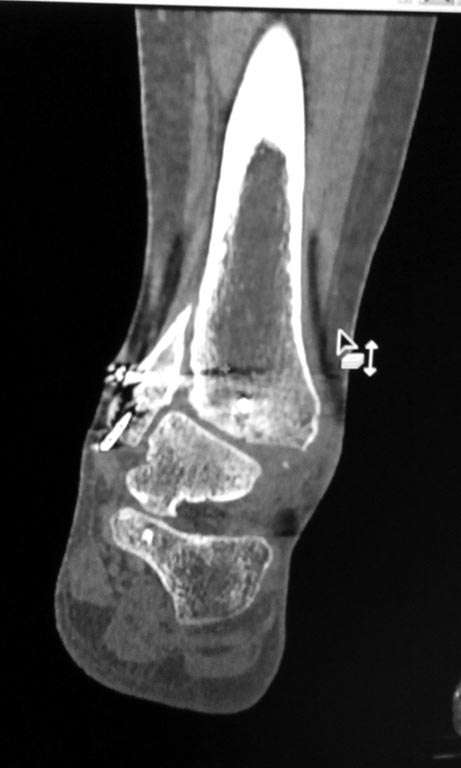

Мужчина, 1987 г.р. получил травму 10.2014. ДТП. Закрытый двухлодыжечный

перелом костей костей левой голени, перелом заднего края большеберцовой

кости с подвывихом стопы кзади, кнаружи. Наложен дистрактор.

Операция 10.2014: закрытая репозиция, остеосинтез спицами,

винтами. В дальнейшем произошло ожидаемое усугубление нарушений

взаимоотношений в голеностопном суставе.

Какой план лечения,на Ваш взгляд, предпочтительнее в данном случае?

Возможно ли одномоментно устранить подвывих или только на аппарате

Иллизарова? Первичные снимки после травмы отсутствуют. Критично ли

"растоптана" латеральная суставная поверхность большеберцовой кости?